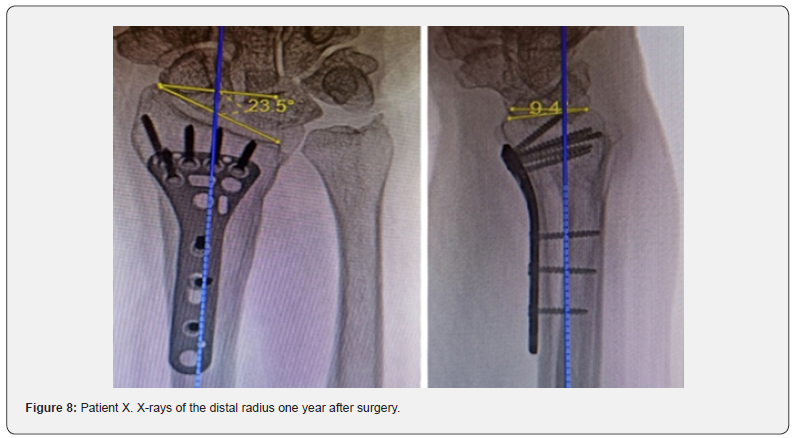

A clinical case. Patient X, a 58-year-old female, presented two months after injury with the diagnosis of a malunited distal radius fracture on the right (AO/ASIF type A 3.2) with delayed carpal tunnel syndrome (DCTS). Upon admission, she complained of wrist deformity, pain, limited range of motion in the right wrist, decreased sensation in fingers 1, 2, and 3, and reduced grip strength. Objectively, the total range of active movements in the right wrist compared to the contralateral limb was 64%, and the gross grip strength was 35%. Pain intensity on the VAS scale reached 4.7 points under load.

X-rays showed angular palmar displacement of the distal radial cortical plate, a reduction in the ulnar-radial angle to 12.3°, an increase in dorsal tilt of the radial joint surface in the sagittal plane to -4° and shortening of the radial bone by 4 mm (Figure 4). Electroneuromyography (ENMG) of the upper extremities revealed a decrease in the M-response of the median nerve at the right wrist (APB-CMAP) and a decrease in sensory conduction velocity of the median nerve (SCV) (Figure 5). According to the classification by A. Żyluk et al. (2014) [25], a severe grade of CTS was diagnosed. The function of the right upper limb on the DASH score was 45.8 points (unsatisfactory). In a planned surgery, from a limited palmar approach to the right wrist, open decompression of the median nerve with epineurotomy and external neurolysis was performed (Figure 6a). Subsequently, through a palmar approach to the forearm, extra-articular open-angle corrective osteotomy and osteosynthesis of the distal radius were performed (Figure 6b).